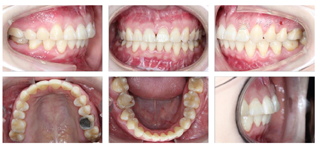

口内检查(图2):

恒牙列,磨牙关系左侧近中,右侧中性,前牙Ⅲ度深覆合,覆盖正常,下颌中线右偏1 mm,左侧前磨牙区开

。

26大面积银汞充填体,46牙色充填体。

32-43对应前庭沟处黏膜可见瘢痕。